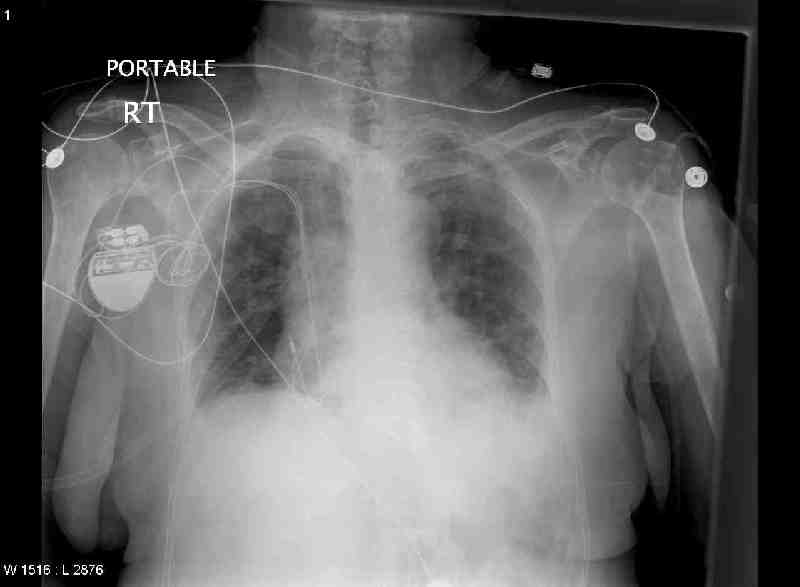

CXR Day 0 (admission day) 4pm

Study Description: CH1/PO

Reason for Study: syncope

Body

No prior studies. Dual chamber pacemaker is adequately

positioned. Small lung volumes are bibasilar atelectasis. No air space

consolidation or frank pulmonary edema.

Impression: pacemaker. Small lung volumes with bibasilar atelectasis and vascular crowding